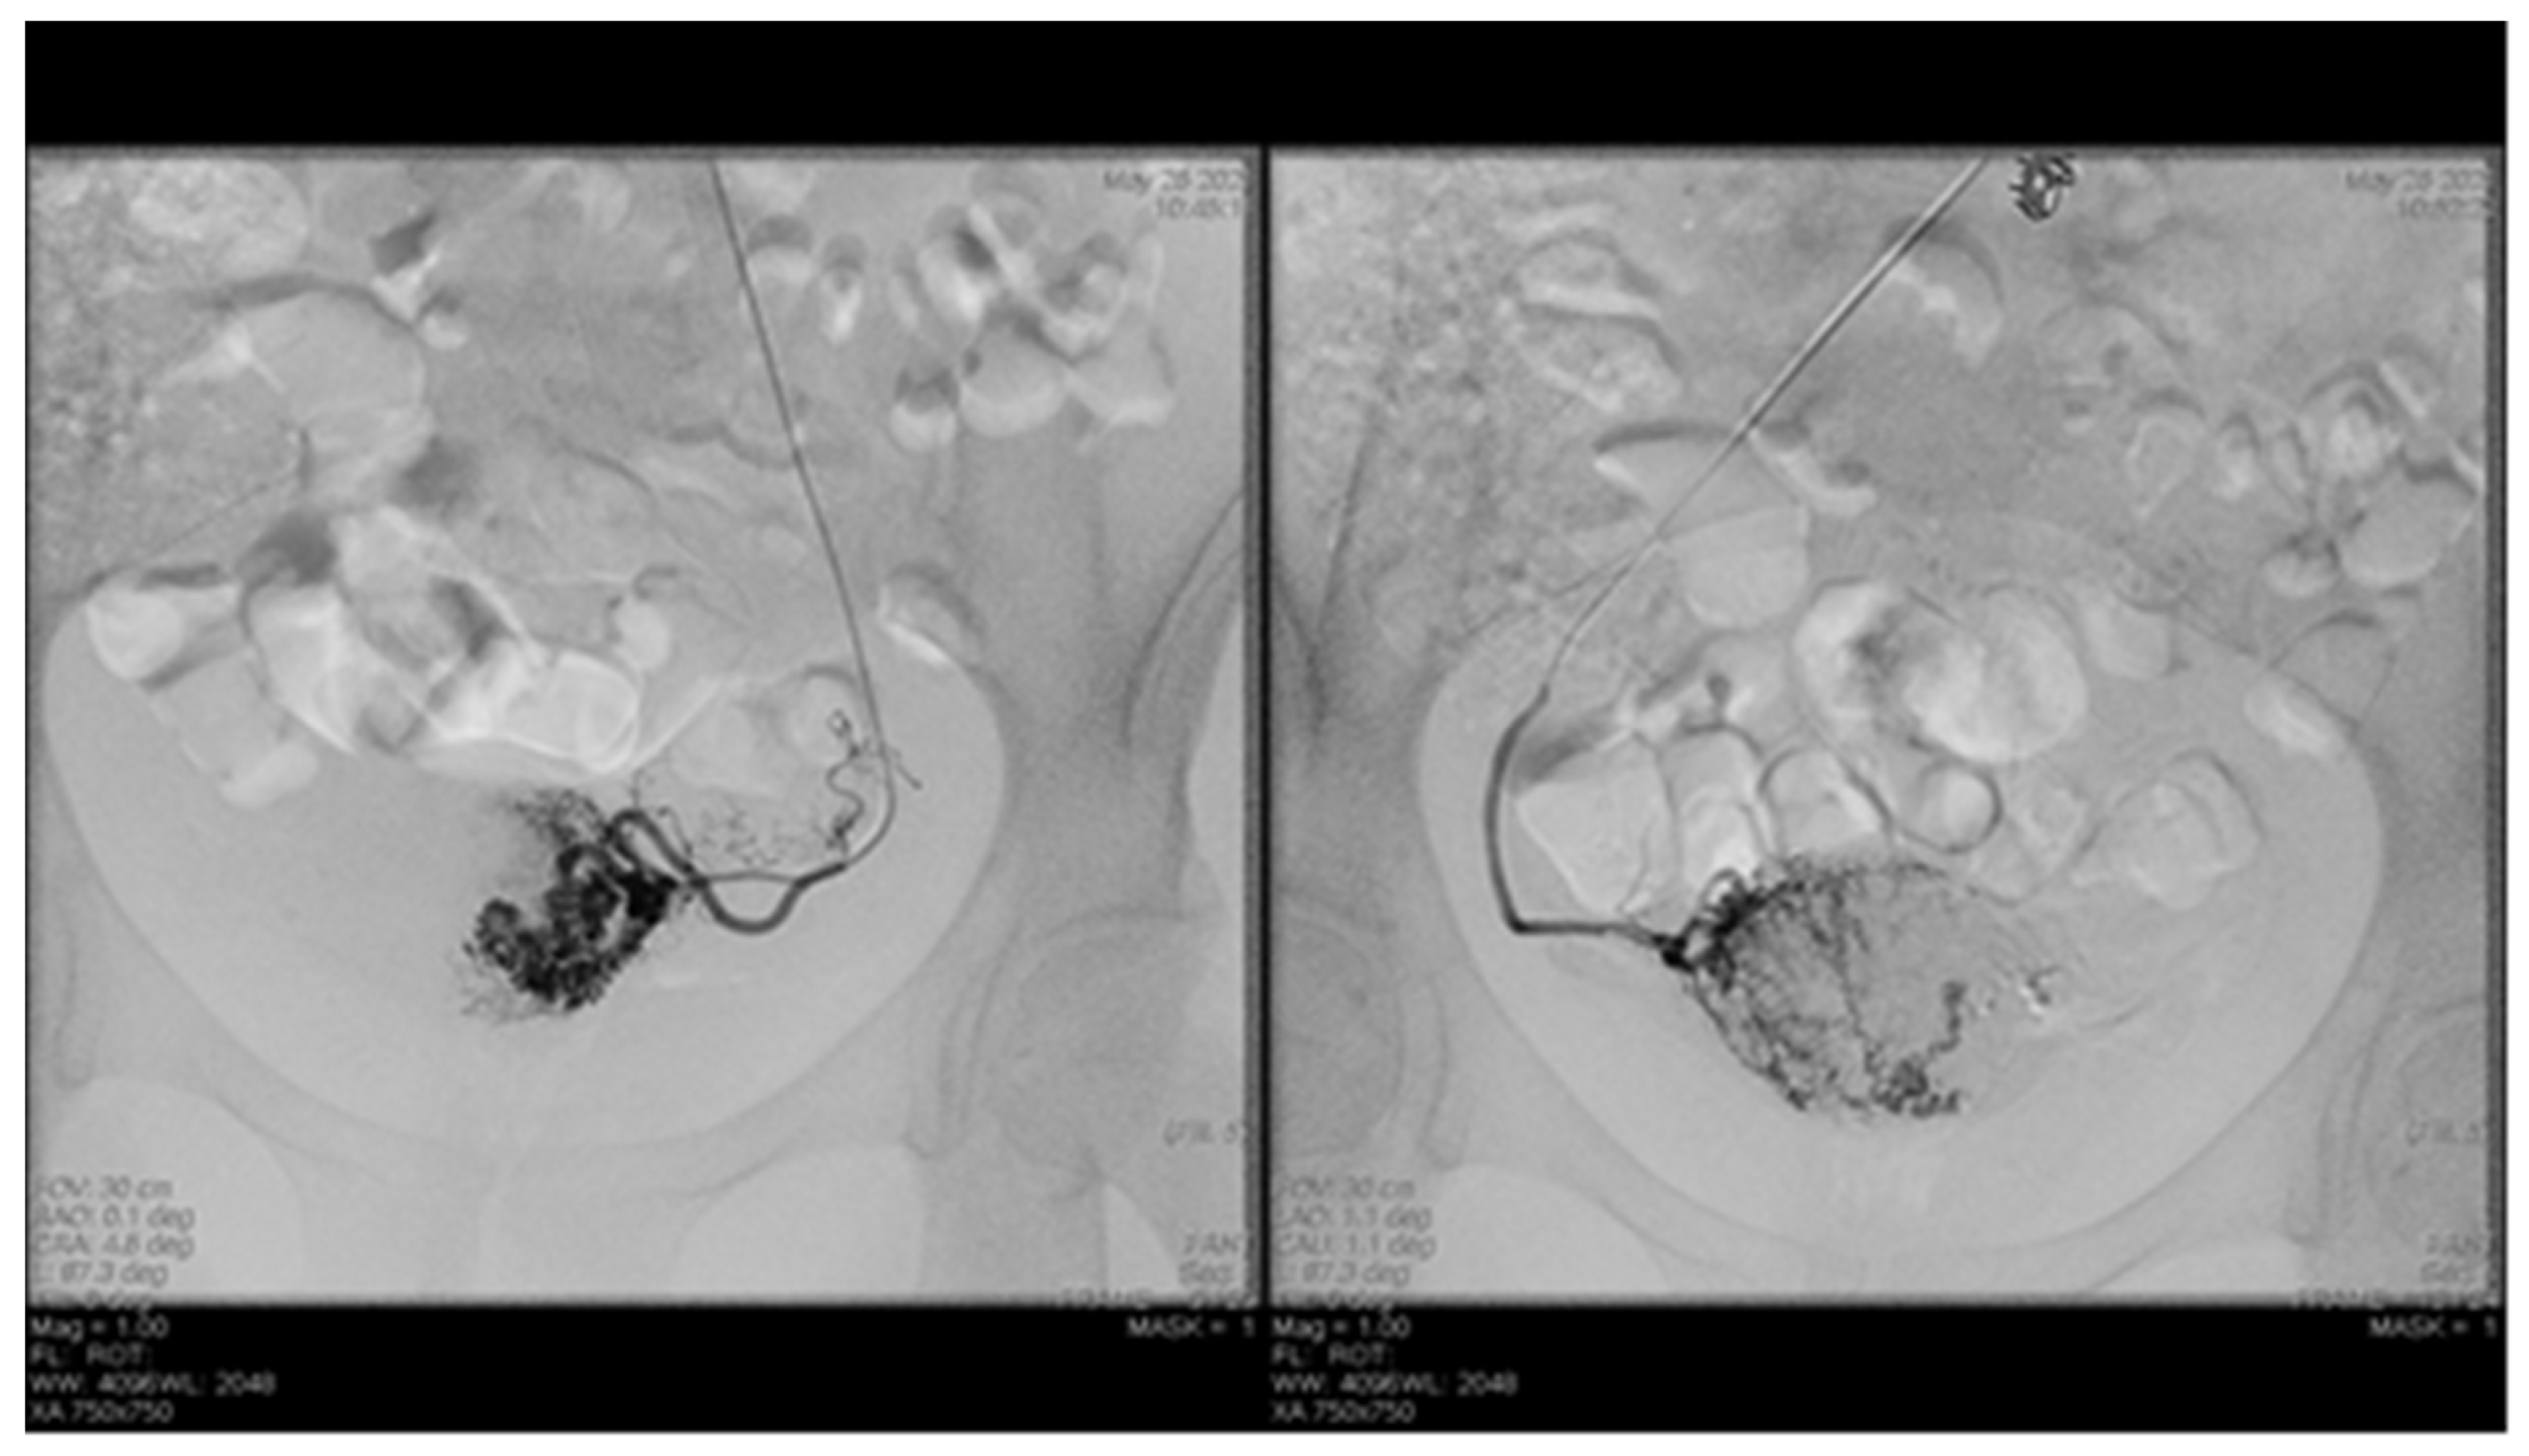

Endovascular procedures were used in 2.29% of cases with ectopic pregnancy (n = 26) (see Figure 4 and Figure 5), 1.23% of patients with arteriovenous malformation (n = 14) (see Figure 6), and 0.52% of patients with major hemorrhage of obstetrical causes (n = 6).

In 97% (n = 1101) of patients, bleeding was stopped after the first attempt of PAE. 3% (n = 34) needed a second embolization. In 12 of 14 cases of AVM, PAE was successful, but in the other two cases, reintervention was needed.

Studies conducted by Jacobowitz et al. and by Ghai et al. support the importance of embolization procedures in bleeding caused by AVM, stating that in some of the cases, re-embolization or even hysterectomy might be needed [2,23,24]. In our study, none of the patients needed hysterectomy, but in two cases we had to reintervene and perform another embolization. Barral et al. concluded that PAE in patients with AVM is effective and does not affect fertility. During the study, they used ethylene vinyl alcohol copolymer [25]. In all our 14 patients with AVM, we used gel-foam, peripherical coils and closure devices.

Figure 6. Selective artery embolization in patient with arterial venous malformation.